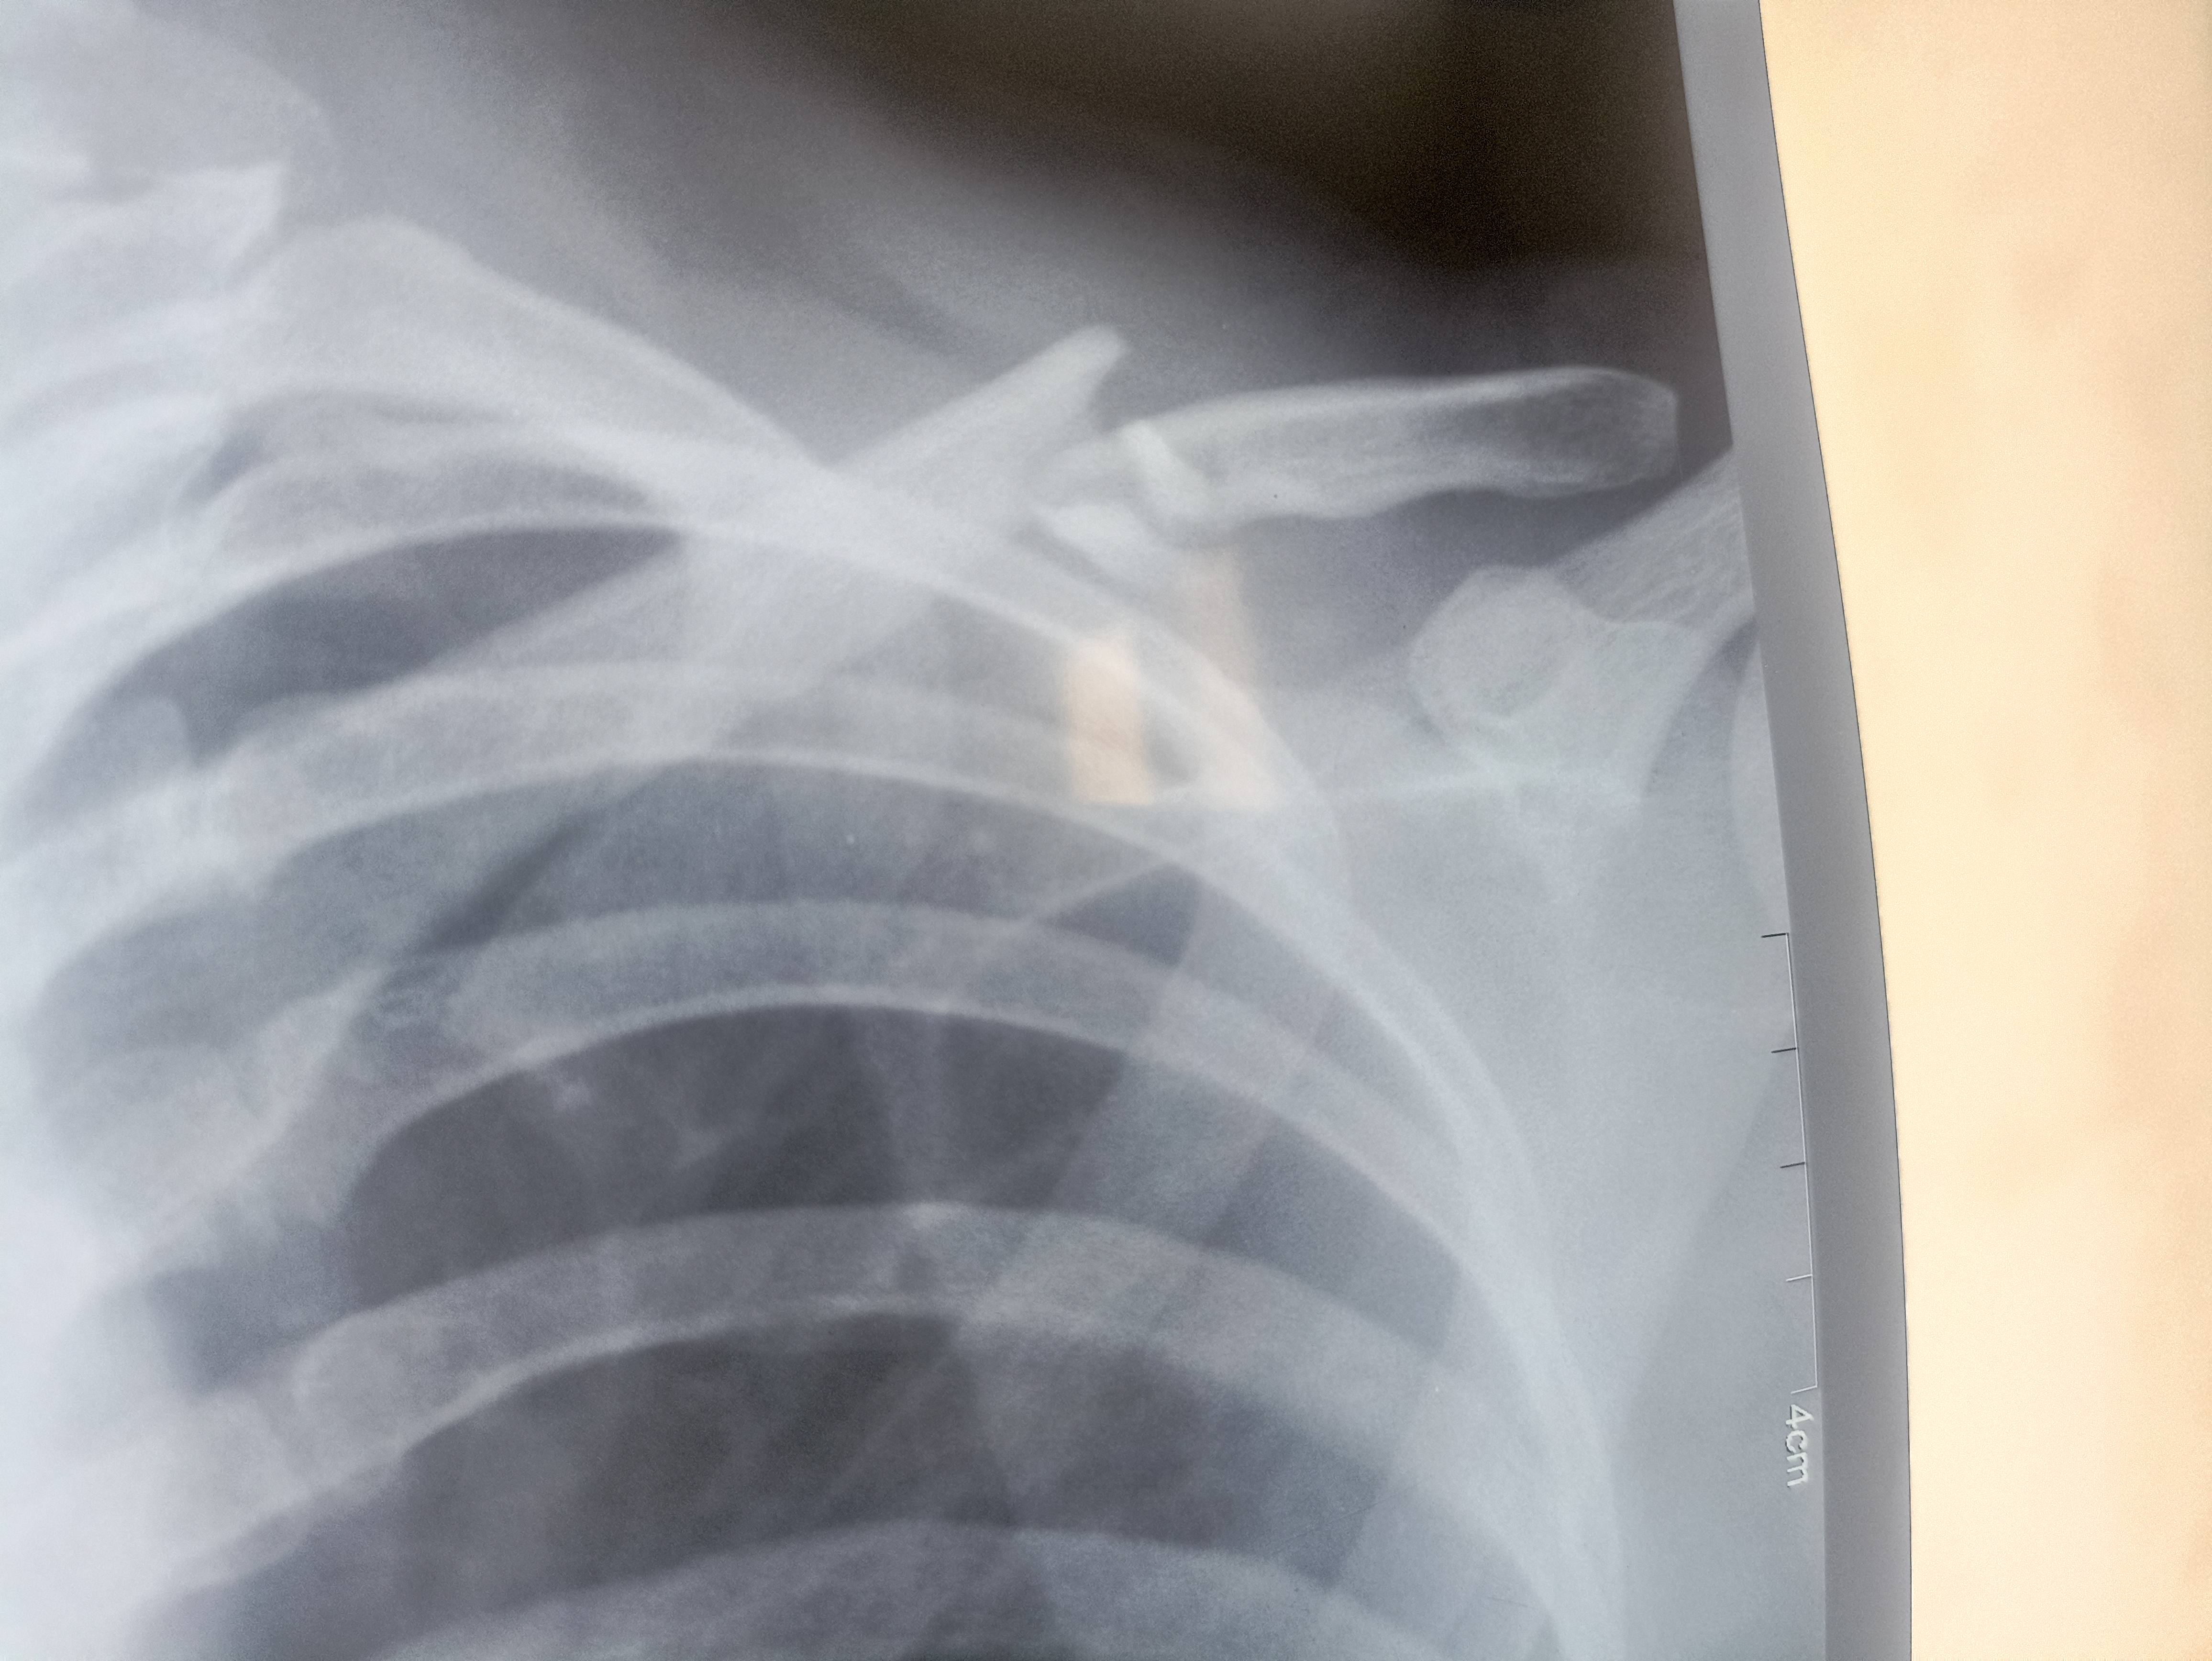

Hi Doctor, my 26 year old sister fallen from scooty and her clavicle bone broken, please find attached x-ray and please advise if surgery necessary or it can fix with belt only